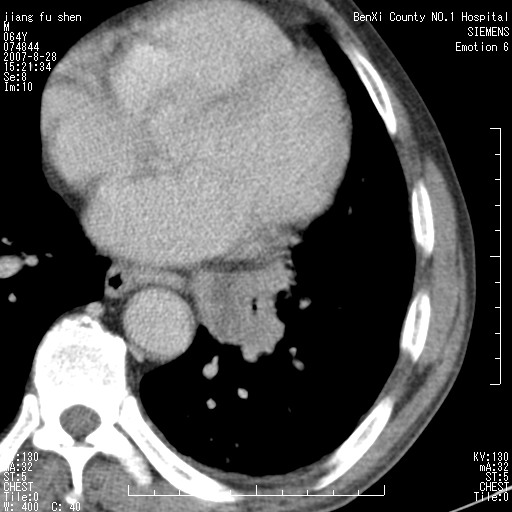

男、64、咳嗽、发烧一周、左肺呼吸音稍弱。既往肺结核,右手结核。

本次扫描患者未带原片,左肺下叶发现病灶。左肺上叶空洞,5组淋巴结肿大,1cm左右。

平扫20-33hu

增强31-33hu

1分半44-52

2分55-67

左肺下叶前内基底段支气管明显偏心性狭窄,周围分叶状肿块,伴有阻塞性肺炎,支持肺癌可能性大。